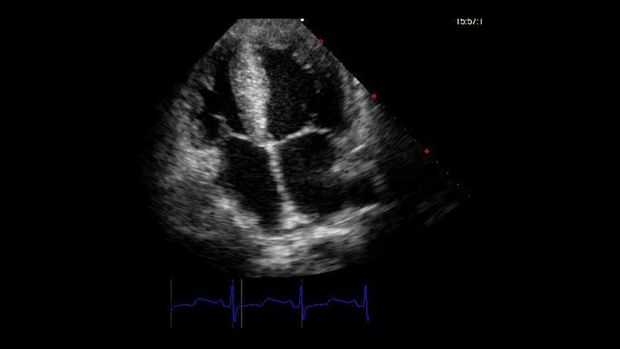

Paso 1: Paso 1: obtener información de entrada del corazón

El marco del programa desarrollado Lee generado solo archivos DICOM (imágenes) exportados desde sistemas de ecocardiografía estándar, automatizar el proceso de transalate estas información en. Archivos STL y enviar el archivo a 3D impresora y del paciente individual expediente médico digital